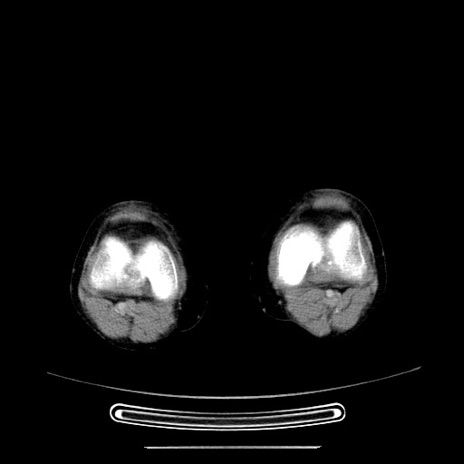

症例5(横断像)

【症例】70歳代女性

【主訴】お腹が張る

【現病歴】1週間くらい前から腹部膨満の自覚あり。昨日夜から増悪したため、本日救急外来受診。

【身体所見】意識清明、BT 36.5℃、BP 165/106mmHg、HR 80bpm、SpO2 98%、腹部:膨満、軟、自発痛・圧痛なし、触診にて不快感あり、腸蠕動音:減弱

【データ】WBC 12600、CRP 1.04